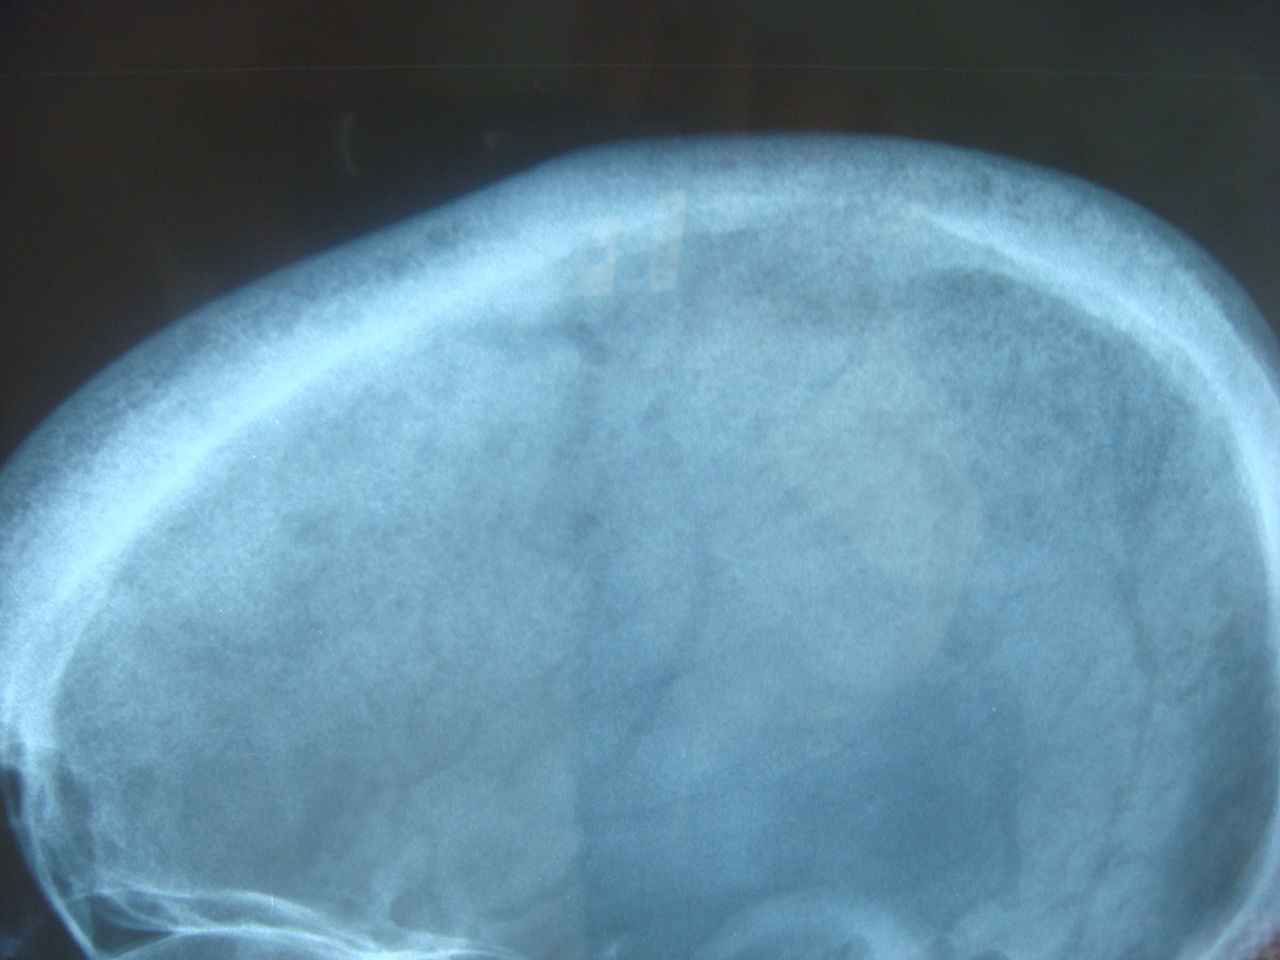

Radiologic findings of hyperparathyroidism. A. Skull Xray shows Salt And Pepper Calvarium Radiology Metabolic bone disease encompasses a diverse group of diseases that diffusely affect. This finding represents tiny spheres of. Calvarial lesions are often asymptomatic and are usually discovered incidentally during computed tomography or magnetic resonance imaging of. Five different infiltration patterns have been described on mri with the “salt. Salt And Pepper Calvarium Radiology.

Hyperparathyroidism x ray wikidoc Salt And Pepper Calvarium Radiology Calvarial lesions are often asymptomatic and are usually discovered incidentally during computed tomography or magnetic resonance imaging of. This finding represents tiny spheres of. Five different infiltration patterns have been described on mri with the “salt. Metabolic bone disease encompasses a diverse group of diseases that diffusely affect. Salt And Pepper Calvarium Radiology.

Salt And Pepper Calvarium Radiology . Metabolic bone disease encompasses a diverse group of diseases that diffusely affect. This finding represents tiny spheres of. Calvarial lesions are often asymptomatic and are usually discovered incidentally during computed tomography or magnetic resonance imaging of. Five different infiltration patterns have been described on mri with the “salt.